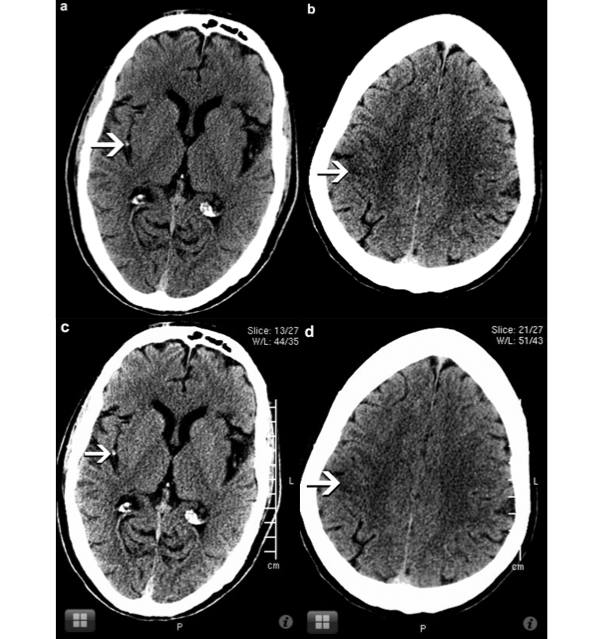

CT Perfusion Quantification Of Small-Vessel RESEARCH Ischemic ...

CT Perfusion Quantification of Small-Vessel Ischemic Severity T.J. Huynh B. Murphy J.A. Pettersen H. Tu D.J. Sahlas L. Zhang S.P A gradation of change may exist between patients with mild and more severe white matter disease. An association between blood brain barrier dysfunction, increasing ... Read More